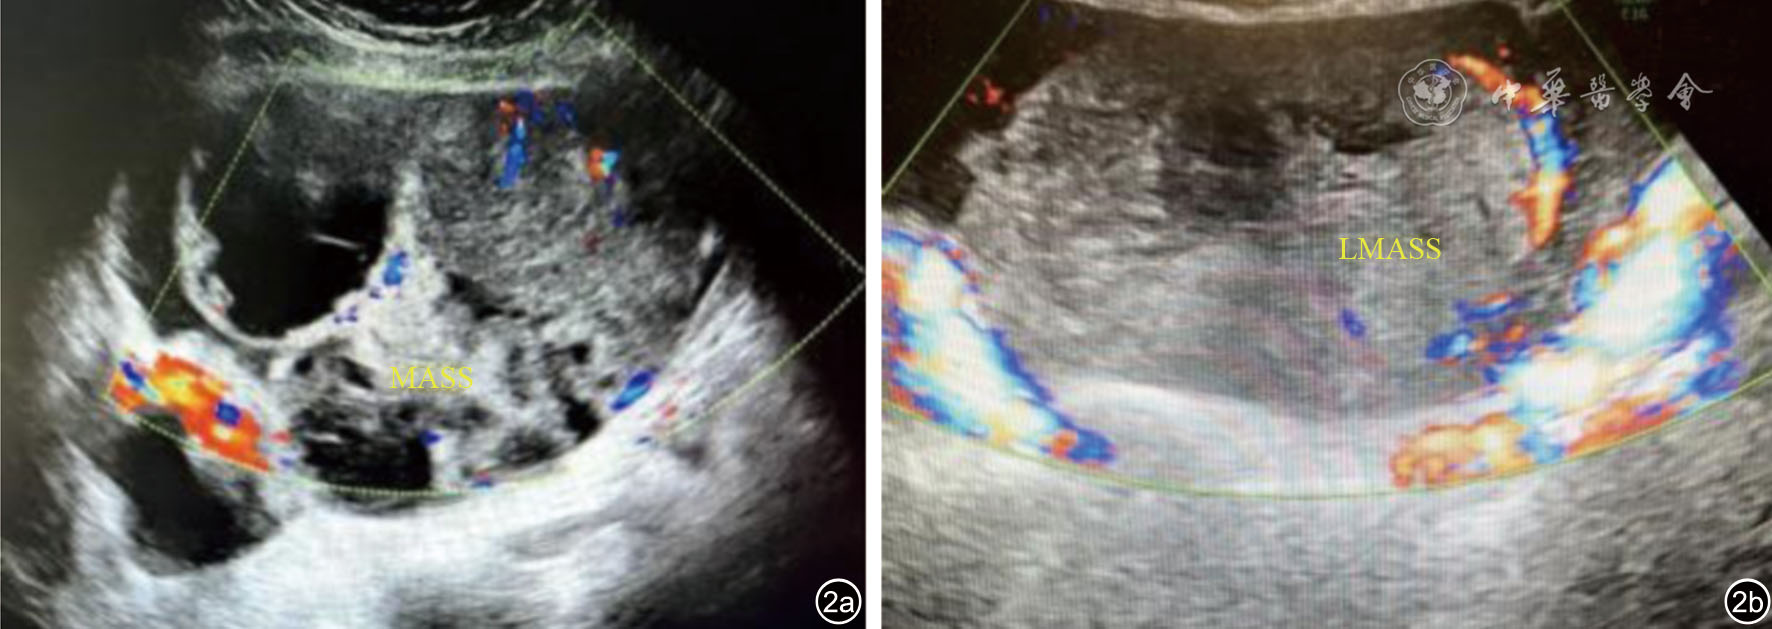

图2 卵巢超声声像图表现。图a(例2)患者38岁,右侧卵巢子宫内膜样腺癌(高-中分化),超声显示右侧卵巢囊实性包块,内见分枝状彩色血流性号,边界清晰;图b(例3)患者44岁,左侧卵巢内膜样腺癌(中分化),超声显示左侧卵巢囊实性包块,以实性为主,内见分枝状彩色血流信号,边界不清晰